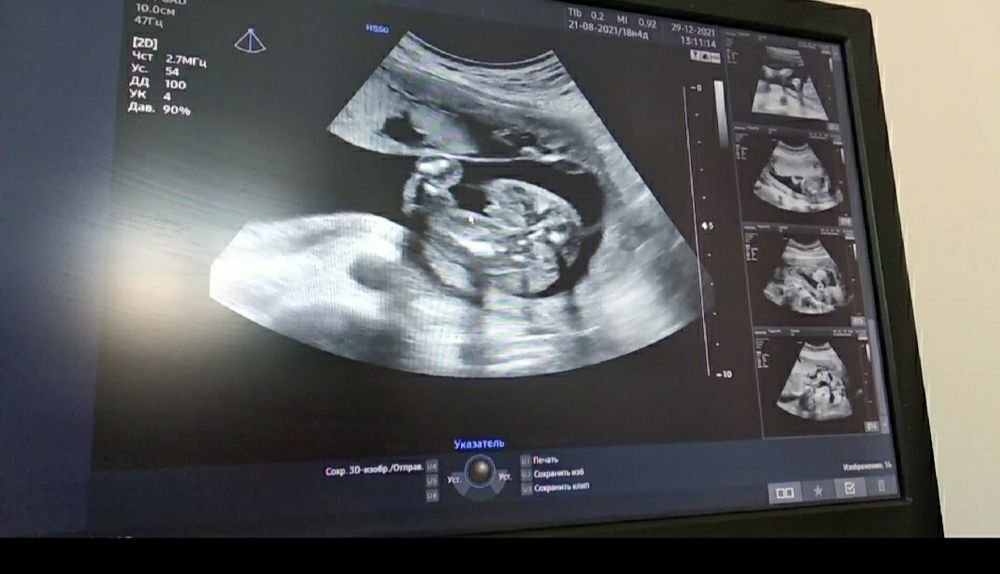

Мама девочки (3 года), жду мальчика, 23 неделя Минск

Мальчик же?

По фото, мне, моим не опытным взглядом кажется, что мальчик) но, врачу виднее. Какой у Вас срок?) мне в Еваклиник врач помню объяснял. Что, к 12 неделе беременности только формируется половая почка и точно сказать срок беременности не возможно. А вот к 15-16 неделе беременности можно точно определить пол. Да и разве так важно, кто у Вас там, мальчик или же девочка. Главное, что бы ребёнок был здоровый)

Инна Быковская, хотим чтобы и мальчик и девочка были) девчуля уже есть) а то муж третьего просить будет) 🤣🤣🤣 По УЗИ 19,1 недель было

Да ну, там уверенно мальчик))

Мальчик! Безалкогольное вино